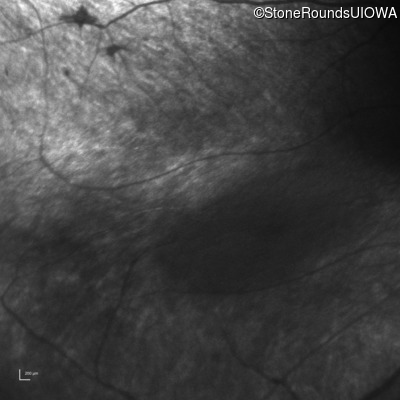

Infrared Fundus Photograph - Right - No Light Perception

Exemplar